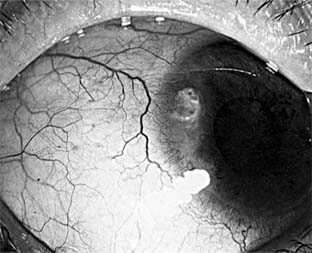

Pneumococcal corneal ulcer usually occurs 24-48 hours after inoculation of an abraded cornea. It typically produces a gray, fairly well circumscribed ulcer that tends to spread erratically from the original site of infection toward the center of the cornea (Figure 6-1). The advancing border shows active ulceration and infiltration as the trailing border begins to heal. (This creeping effect suggested the term "acute serpiginous ulcer.") The superficial corneal layers become involved first and then the deep parenchyma. The cornea surrounding the ulcer is often clear. Hypopyon is common. Scrapings from the leading edge of a pneumococcal corneal ulcer usually contain gram-positive lancet-shaped diplococci. Drugs recommended for use in treatment are listed in Tables 6-2 and 6-3. Concurrent dacryocystitis should also be treated.

Figure 6-1

Figure 6-1: Pneumococcal corneal ulcer with hypopyon.